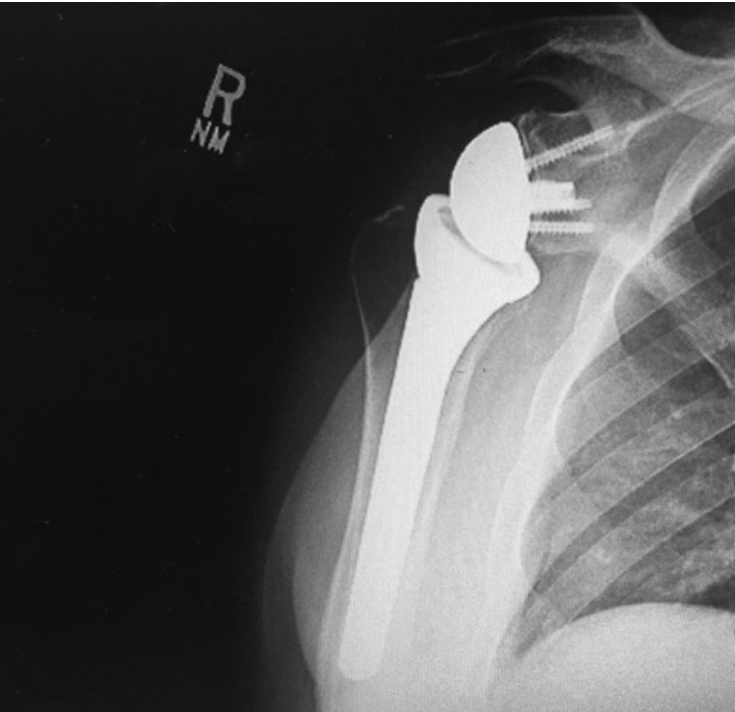

A reverse shoulder replacement is a procedure used primarily in

patients who have shoulder joint arthritis and torn, irreparable rotator

cuff tendons. In this procedure, the humeral head is resected and a

metallic rod is inserted into the humerus with a cup attached to the top

of it. The bony socket is replaced with a metallic ball with screws

securing it, thereby “reversing” the ball and socket joint. The physics

of aligning the replacement parts in this manner gives the replacement

parts stability that would not be possible with a standard shoulder

replacement. This type of replacement requires a functioning deltoid

shoulder muscle as well as intact nerve function for the shoulder.